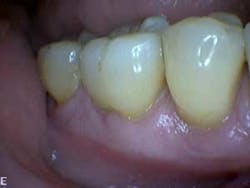

At the three-month periodontal maintenance appointment, the patient’s gingival color was pink with no sign of inflammation (figures 7–9).

Clinical presentation three months after LANAP treatment (figures 7–9)